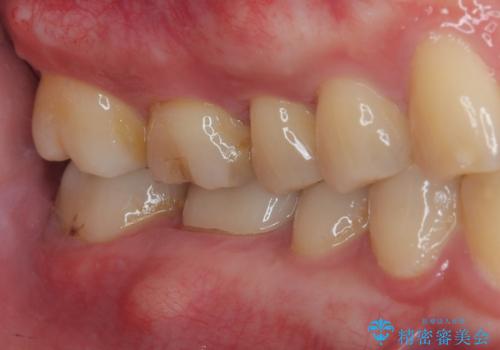

- 歯が割れたことを主訴に来院された患者様です。割れた原因としては噛み合う歯が強化セラミックスのみでできたフルジルコニアクラウンであったことと、大きな詰め物が入っていて自分自身の歯の範囲が少なかったことが考えられます。応急で来院されたときには暫間的に強力な接着剤で固定しました。

CT を撮影して確認したところ、歯肉より4ミリ程度深い場所で破折していました。患者様と相談して、外科的な介入はせずに被せもののみでの治療を行うこととしました。

拡大鏡視野下で詰め物と虫歯の除去を行い、詰め物の範囲が大きかったためオールセラミッククラウンに適した形に整えました。